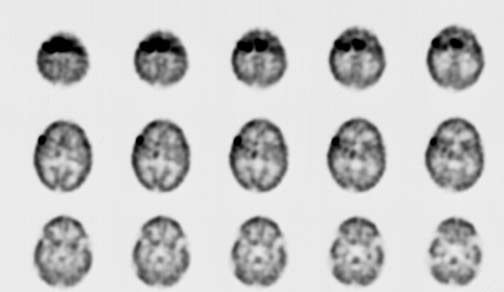

CaseHE02

- Age/Sex: 3 M

- Chief Complaint: けいれん発作重積状態

- Images:

- Tc-99m ECD Aug/27

- Tc-99m ECD Aug/31